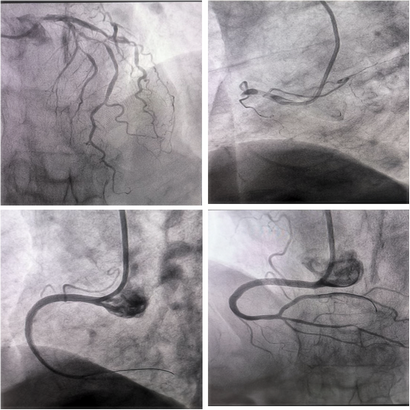

当造影成像清晰呈现出血管狭窄程度的那一刻,在场的每一个人都不禁倒吸一口凉气。患者刘阿姨年事已高,血管堵塞情况异常严重,每一秒的拖延都可能带来无法挽回的后果。心内科四病区医生深知情况危急,迅速且全面地向家属告知病情后,即刻启动了PCI(冠状动脉支架植入术)治疗方案。

手术过程中,吴晓杰主任、李景瑞副主任等全神贯注、精准操作,刘阿姨也凭借顽强的意志积极配合。时间在紧张的氛围中飞速流逝,好在这场与死神的较量最终迎来了胜利曙光,冠状动脉支架成功植入,刘阿姨鲜活的生命得以挽救 。术后,医生与家属交流时感慨万分,刘阿姨能在如此紧急的状况下及时赶到医院,无疑是不幸中的万幸。

堵塞血管

急诊PCI介入手术